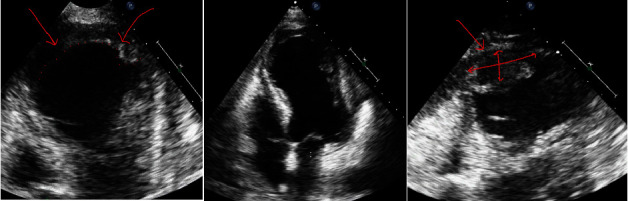

心室壁破裂与急性心肌梗死后的不良预后有关。我们描述了一例经皮冠状动脉介入治疗后心肌梗死心尖壁破裂的病例。我们的病例强调了迅速评估、诊断和处理的重要性,以提高面临这种危急情况的患者的存活率。

Ventricular wall rupture is associated with poor outcomes subsequent to an acute myocardial infarction. We describe a case of postmyocardial infarction apical wall rupture following percutaneous coronary intervention. Our case emphasizes the importance of swift evaluation, diagnosis, and management to enhance survival in individuals confronting this critical condition.